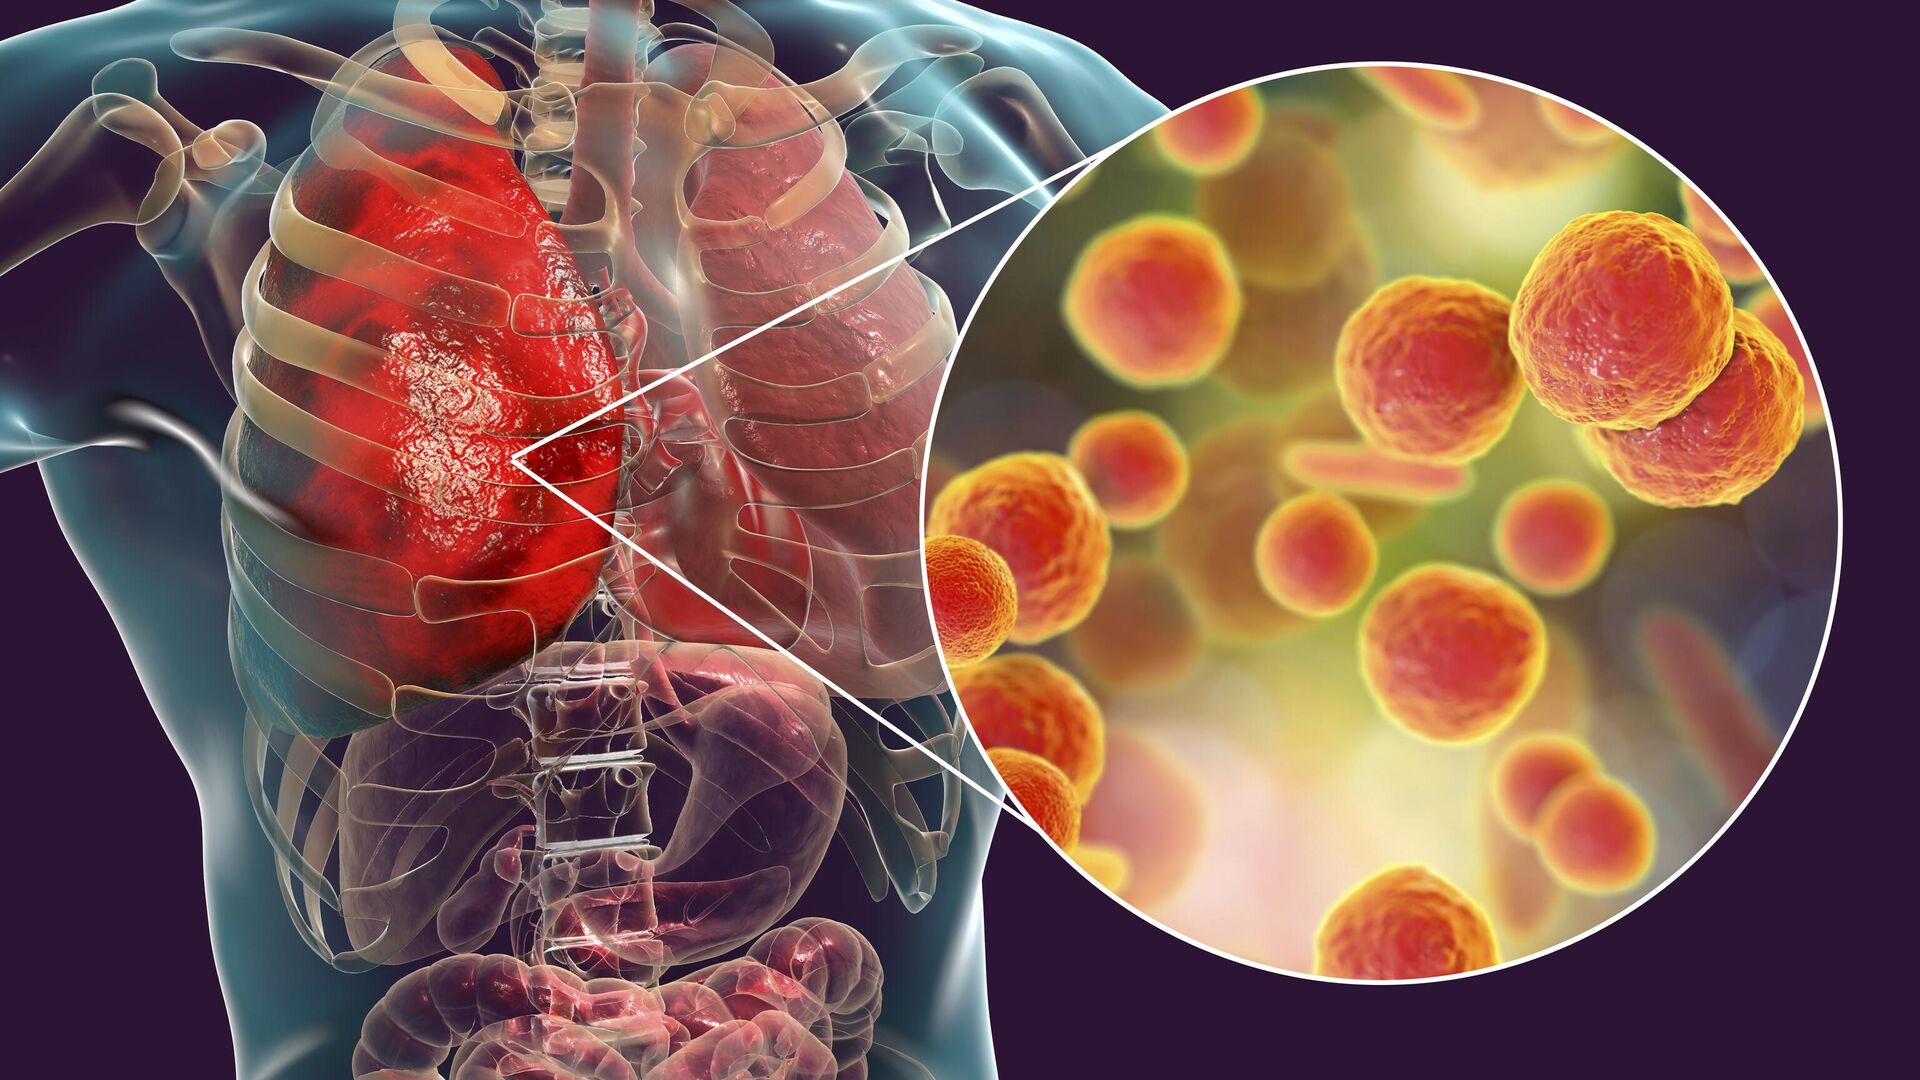

Фотографии бактерий, вызывающих бактериальные пневмонии у животных

Раздел: Другие животные